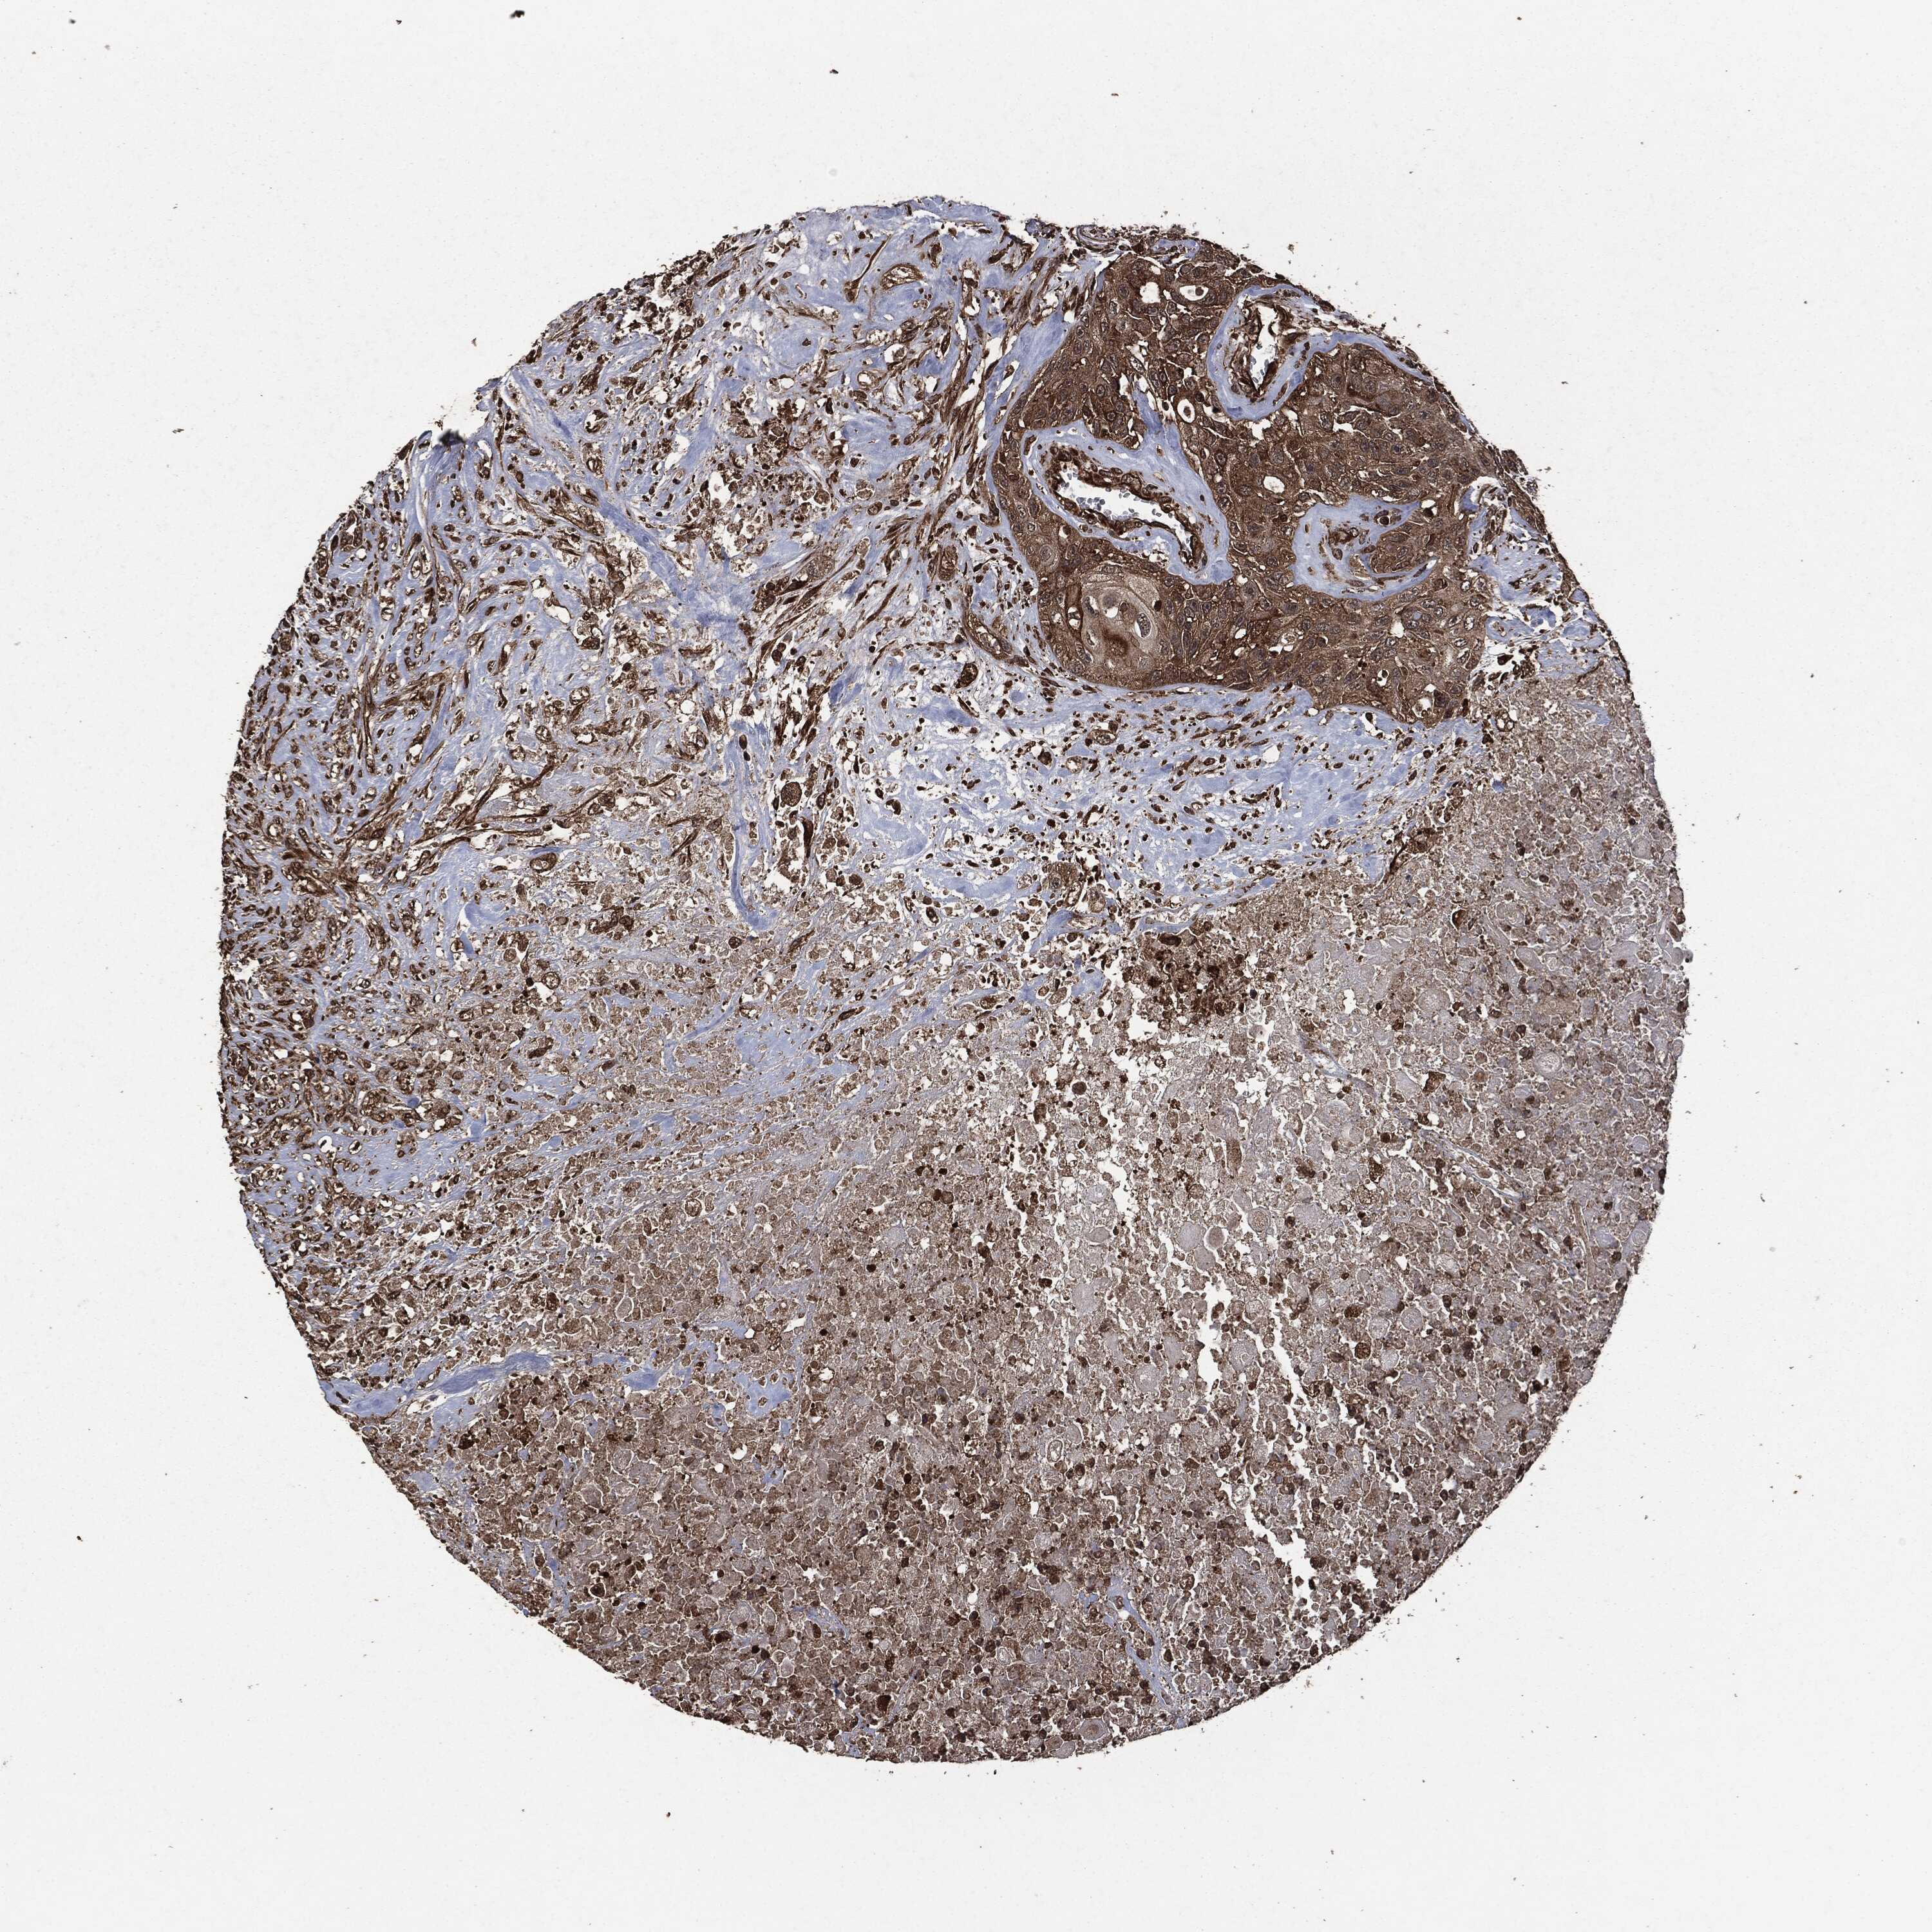

UROTHELIAL CANCER - Protein expressioni

A mouse-over function shows sample information and annotation data. Click on an image to view it in a full screen mode. Samples can be filtered based on level of antibody staining by selecting one or several of the following categories: high, medium, low and not detected. The assay and annotation is described here.

Note that samples used for immunohistochemistry by the Human Protein Atlas do not correspond to samples in the TCGA dataset.

Antibody stainingi

Antibody staining in the annotated cell types in the current human tissue is reported as not detected, low, medium, or high, based on conventional immunohistochemistry profiling in selected tissues. This score is based on the combination of the staining intensity and fraction of stained cells.

Each image is clickable and will lead to virtual microscopy that enables deeper exploration of all samples and also displays staining intensity scores, fraction scores and subcellular localization as well as patient and tissue information for each sample.

HPA049830

CAB002015

CAB080330

CAB080331

CAB080332

Urothelial carcinoma, High grade

Urothelial carcinoma, NOS

Urothelial carcinoma, Low grade

Adenocarcinoma, NOS